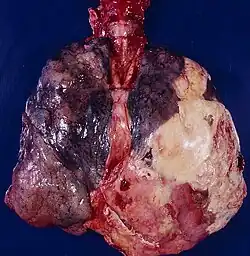

Левое лёгкое, окружённое толстым слоем гнойного экссудата — картина, соответствующая эмпиеме плевры.